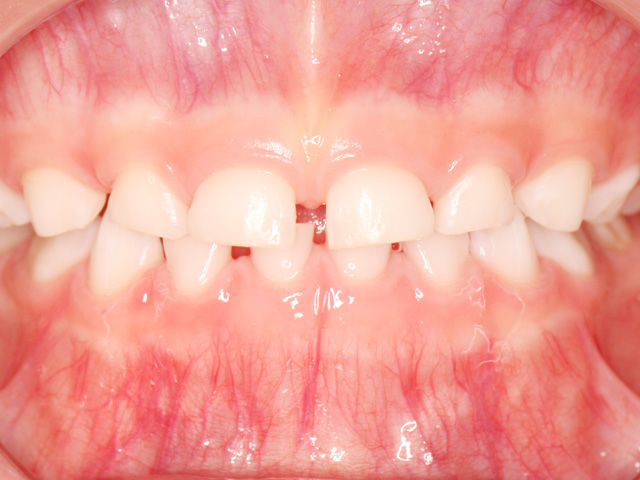

笑ったときに前歯が出ている、噛み合わせがズレている、歯が重なって生えてきている…。実はこれらは、成長とともに自然に治ることもあれば、逆に悪化してしまうケースもあります。

例えば、顎が小さいと、永久歯が生えるスペースが足りず、歯が重なったり、外に押し出されたりします。これを無理に並べようとすると、大人の矯正では抜歯が必要になることもあります。しかし、成長期に顎の幅を広げておけば、そもそも抜歯をしなくても済む可能性が高くなるのです。小児矯正では、装置を使って顎の成長方向を誘導したり、舌や唇の使い方、呼吸の仕方といった口周りの癖を改善することもあります。これらは歯並びに大きな影響を与える要素であり、見過ごされがちですが非常に重要です。

実際の診療では、「様子を見ていたら、かえって歯並びが悪化してしまった」というケースも少なくありません。特に顎が小さい傾向のあるお子さんは、永久歯が生えるスペースが足りず、重なりや出っ歯として現れてきます。